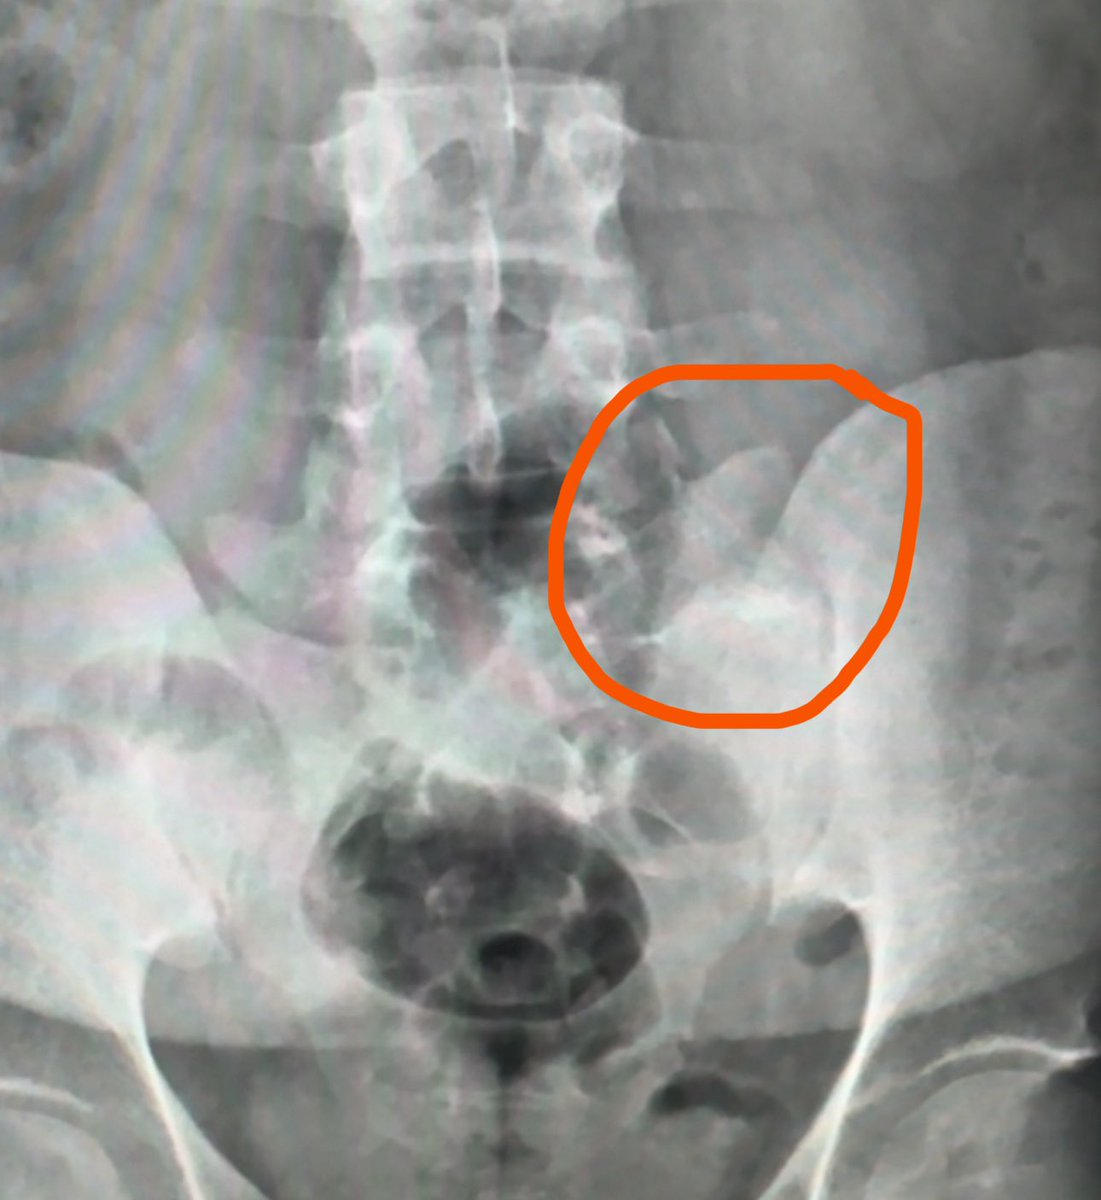

مريض يرفض اجراء الأشعة السينية ( x-ray ) معلّلاً بأن اشعة الرنين المغناطيسي ( MRI) ستجيب على كل الأسئلة⁉️ على الرغم من دقّة أشعة الرنين المغناطيسي العالية لدى كثير من المرضى الذين يشتكون من ألم اسفل الظهر ، إلا أن أهمية إجراء الأشعة السينية أحيانًا لا يقل دورها عن دور الرنين